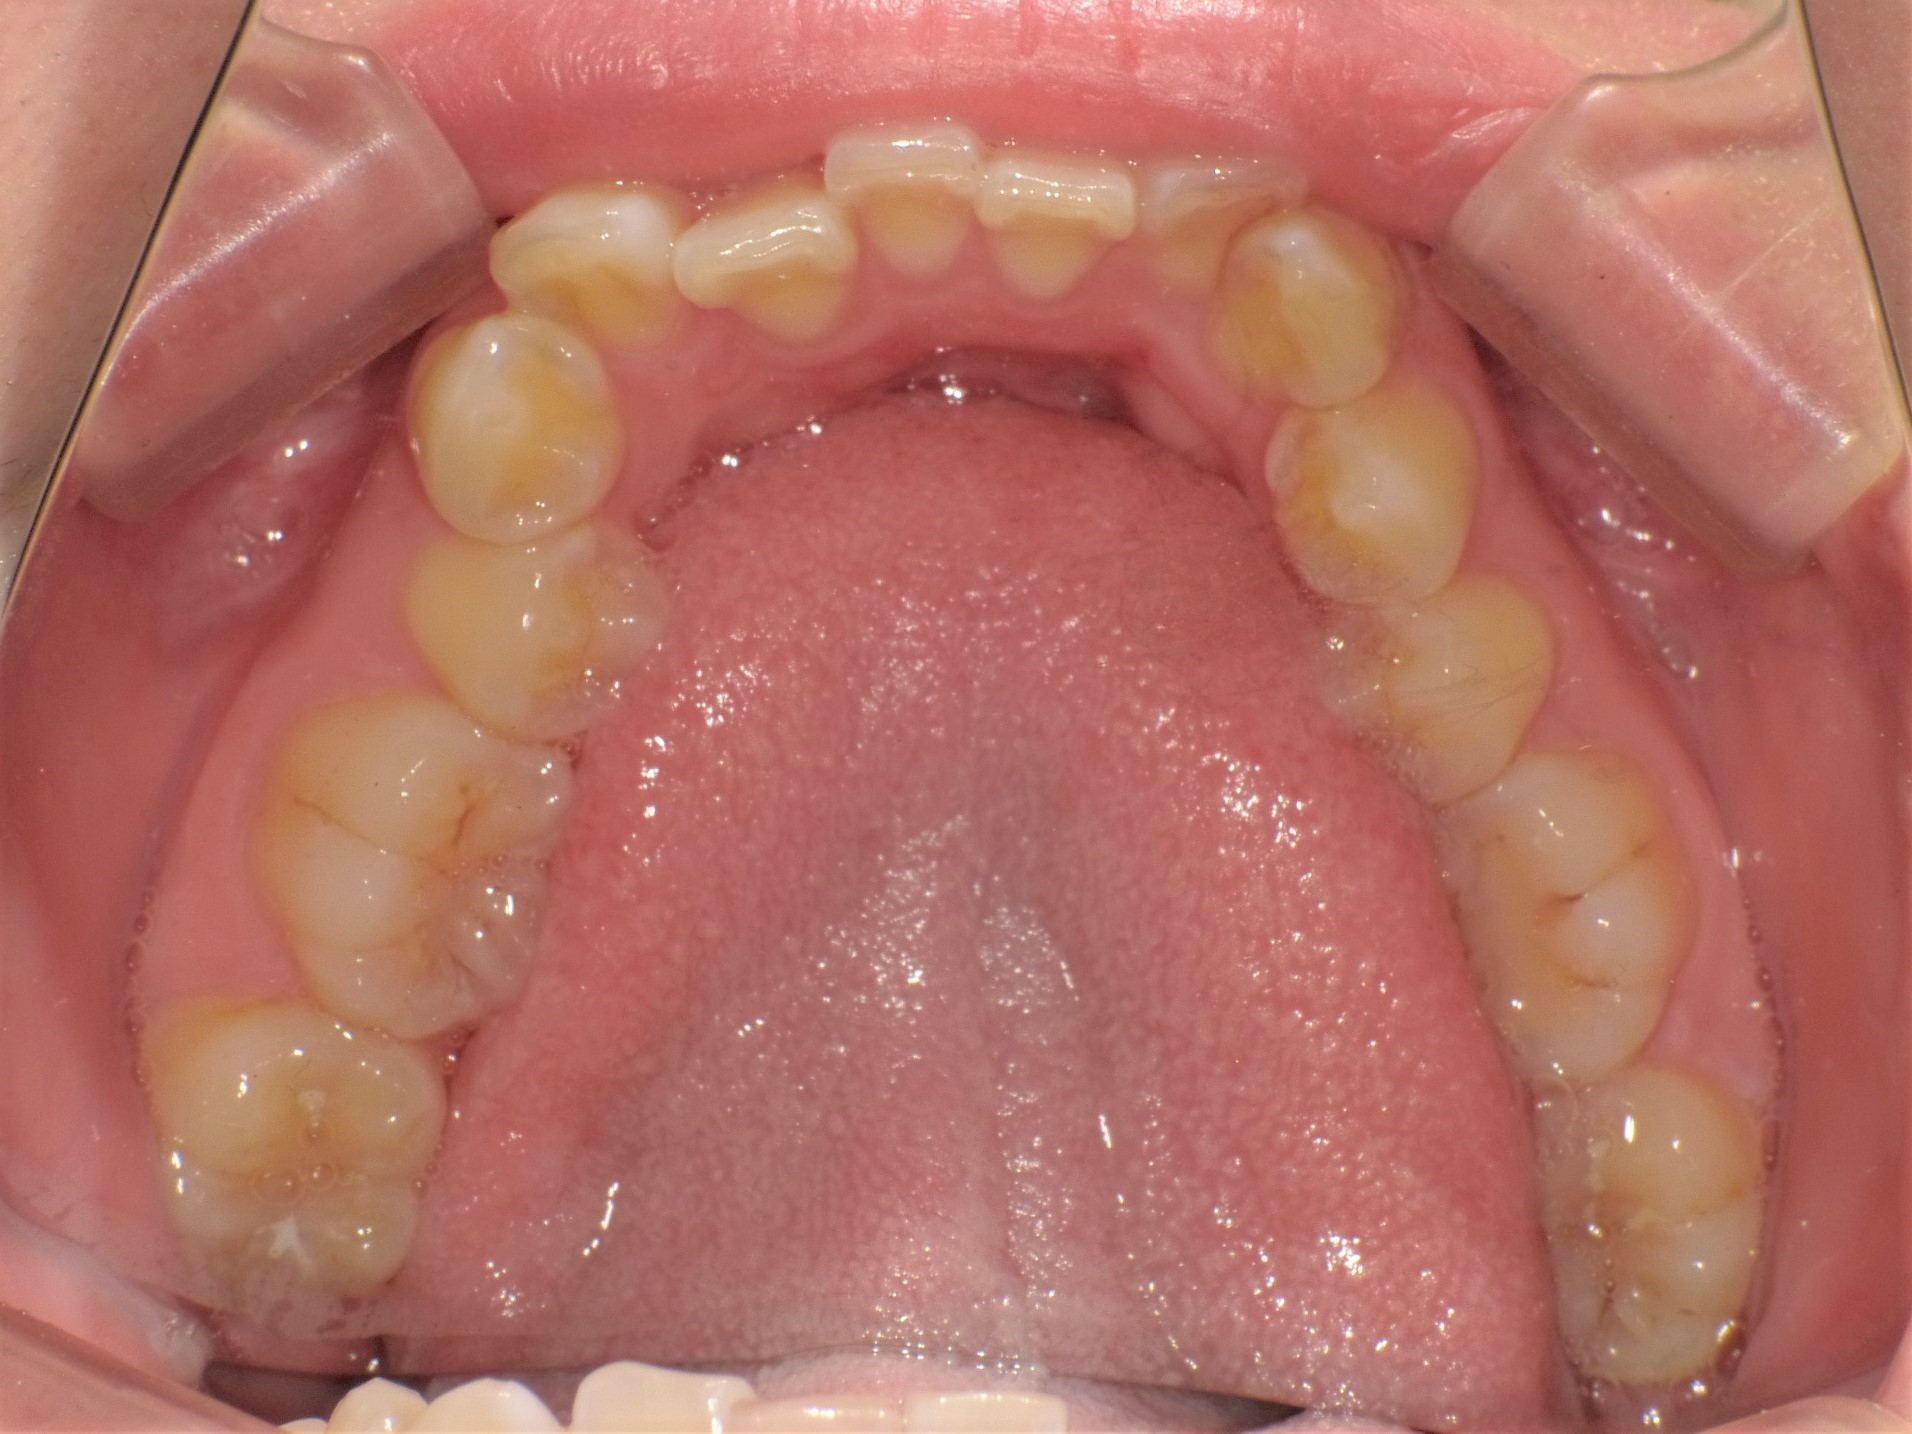

インビザライン(マウスピース矯正)治療中の方の写真になります(^^)

下の写真見比べていただくとわかると思うのですが前歯が綺麗に並び始めてきました☆